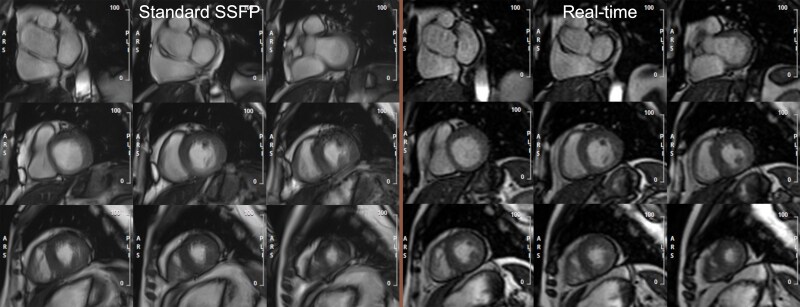

Aims: Cardiovascular magnetic resonance (CMR) is established as the reference standard for cardiac volumetric assessment. Despite the accuracy and robustness of steady-state free precession (SSFP) cine imaging, its use may prove challenging in patients with arrhythmia and in those who cannot perform repeated breath holds. An alternative solution may be a free-breathing electrocardiogram (ECG)-triggered, retro-gated, real-time cine sequence. This study sought to compare left ventricular volumetric, wall motion, and thickness assessment with both techniques.

Methods and results: Consecutive patients with known or suspected cardiac disease referred for clinical CMR were studied at 3-Tesla. Participants underwent short-axis standard SSFP and real-time cine imaging in a randomized order within the same scan. Between sequence agreement and mean difference were compared for end-diastolic volume (EDV), end-systolic volume (ESV), stroke volume, ejection fraction (EF), left ventricular mass (LVM), maximal wall thickness (MWT), and wall motion score index (WMSi). Two hundred and two patients (mean age 61 ± 14 years, 51% male and 14% irregular rhythm) were studied. All left ventricular indices showed good-excellent agreement between the two methods [intraclass correlation coefficient (95% confidence interval), EDV 0.96 (0.95-0.97), ESV 0.96 (0.94-0.97), EF 0.85 (0.81-0.88), LVM 0.93 (0.91-0.95), MWT 0.80 (0.75-0.85), and WMSi 0.93 (0.91-0.95)].

Conclusion: In patients with known or suspected cardiac disease, real-time cine imaging demonstrates good-excellent reproducibility of LV volumetric, wall thickness and resting wall motion assessment when compared with standard SSFP (Trial registration: NCT05221853).